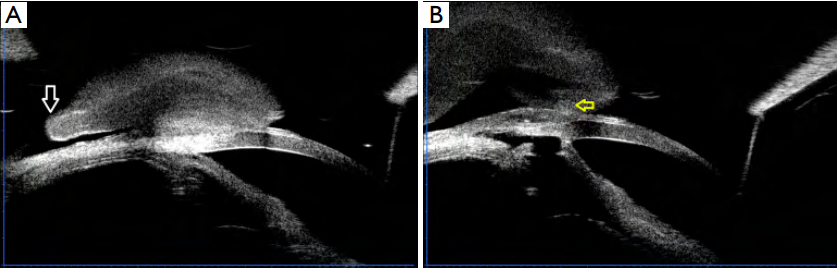

(Figure 1C). Ultrasound biomicroscopy (UBM) confirmed

that the bleb was connected to the conjunctiva through a

thin base with partial free edge (Figure 2A), and the inner

path of the ff ltration bleb was patent (Figure 2B).

Figure 2 Ultrasound biomicroscopy showed that the bleb was connected to the conjunctiva through a thin base with a partial free edge

(A).

The inner passage of the ff ltration bleb was patent (B). White arrow: partial free edge. Yellow arrow: inner passage of the ff ltration bleb.